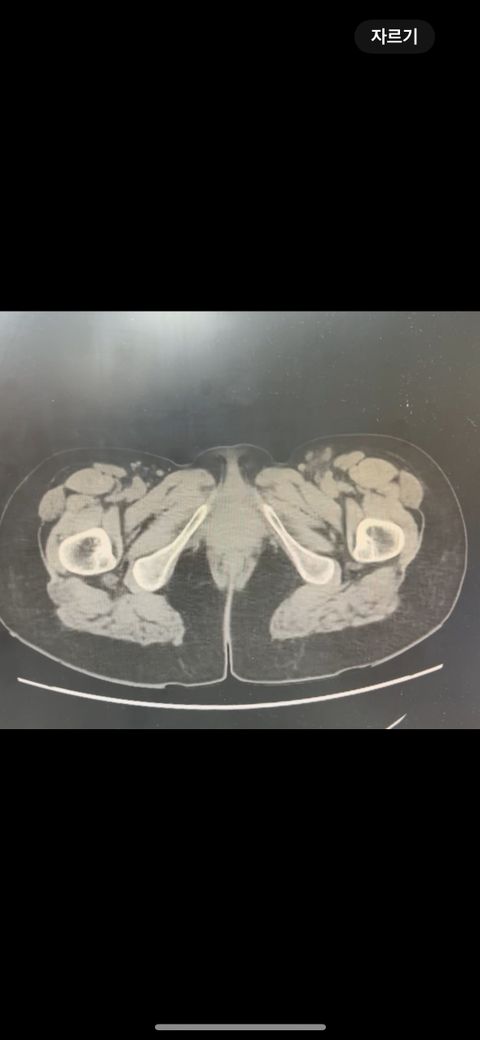

복부 ct (contrast) 영상 판독해주세요!!

어제 복부 ct 촬영하였는데 판독 하려면 시간이 걸려서 미리 알 수 있을까요? 지금 증상은 윗배가 많이 나왔고 허리 아프고 조금만 밥 먹어도 배부른 상태입니다..

어제 말씀드린대로 자궁 쪽에 불규칙한 음영들이 보이고 있어 물혹이 있는 것으로 의심해 볼 수 있으며, 이외에 복부에 가스가 조금 차있거나 비장이 약간 커져 있는 듯한 모습이 보이나 일부 단면만으로 유추한 것이라 판독 상 틀릴 가능성도 있겠습니다.